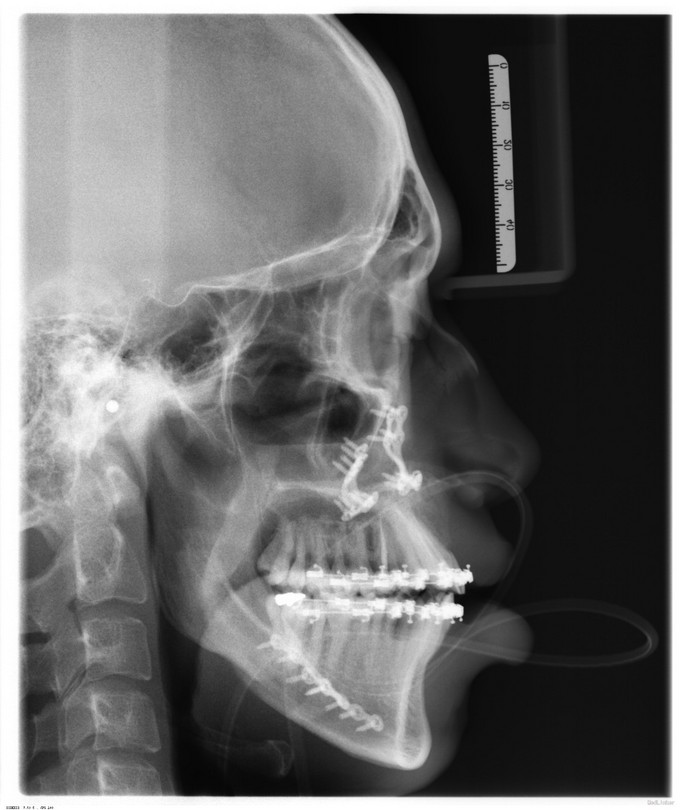

自觉上颌后缩 ,下颌前突数年。

面部发育良好,中线左右对称,上中下比例协调,面下三分一过长前突,颏顶点正中。左侧颞下颌关节无弹响无疼痛动度正常,右侧颞下颌关节开口末期可触及绞索感,无弹响无疼痛动度正常。张口度5.5cm,开口型正常。上下牙弓关系不协调,前牙反牙合后牙近中错牙合,龋齿无,牙周病无。

诊断:1.上颌后缩2.下颌前突,全麻下行上颌LeFortⅠ型截骨前徙术+双侧上颌骨骨内坚固内固定术+双侧下颌骨矢状劈开后退术+去骨皮质术+坚固内固定术+双侧邻近瓣转移修复术。